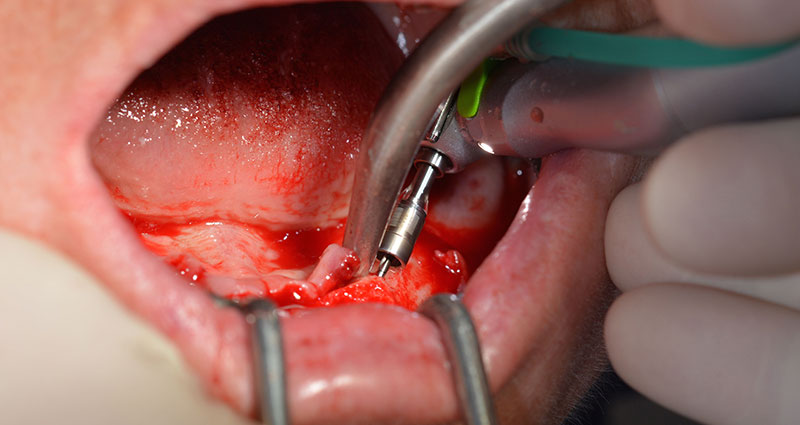

A continuación, se identificó el agujero mentoniano (foramen mentale) como la estructura anatómica límite y se alisó el cortical de la cresta ósea con la pieza de mano recta y una fresa redonda grande (fig. 4).

Es en este momento, donde se hacen patentes las primeras ventajas de Implantmed. El protocolo quirúrgico ya está predefinido y guardado en distintas posiciones fijas que pueden seleccionarse con solo pisar el pedal en la posición «P» o desde la propia pantalla. En este caso, la pantalla iluminada también muestra en grande la velocidad de 35 000/rpm preajustada en la posición 1 (figs. 5 y 6).

El protocolo quirúrgico de los implantes utilizados (SKY, bredent medical) prescribe una velocidad de 1 200/rpm para las perforaciones piloto (figs. 7-9).

Este valor se corresponde con la posición siguiente del ajuste predefinido en Implantmed. Aquí se aprecia la inclinación de aproximadamente 45 grados del contra-ángulo de W&H hacia medio caudal en la región de la pieza 45 para preservar el nervus mentalis. El foramen mentale sirve como orientación anatómica para todas las perforaciones en esta zona. Las perforaciones siguientes se realizaron con una velocidad reducida de 300/rpm (figs. 10 y 11).